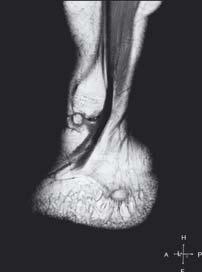

zwyrodnieniowa stawu skokowo-goleniowego

Staw skokowy dolny